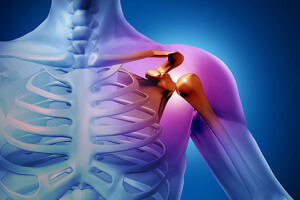

Плечо, как самая активно действующая часть организма, страдает чаще. Поражение плечевого сустава занимает более 50% случаев.

Такое несоответствие, хоть оно и несколько компенсируется выростом края лопатки (суставной губой), все же увеличивает риск вывиха этого сустава.

Близко расположены кровеносные сосуды и нервные стволы, которые будут повреждены при вывихе.

Особенности строения плечевого сустава приводят к неизбежным повреждениям окружающих тканей:

- Разрыв капсулы сустава разной степени;

- Отрыв связок от края лопатки;

- Вдавление и деформация головки плечевой кости;

- Отрыв бугорков кости вместе с мышцами и связками.

Головка плечевой кости в момент вывиха может смещаться в разные стороны.